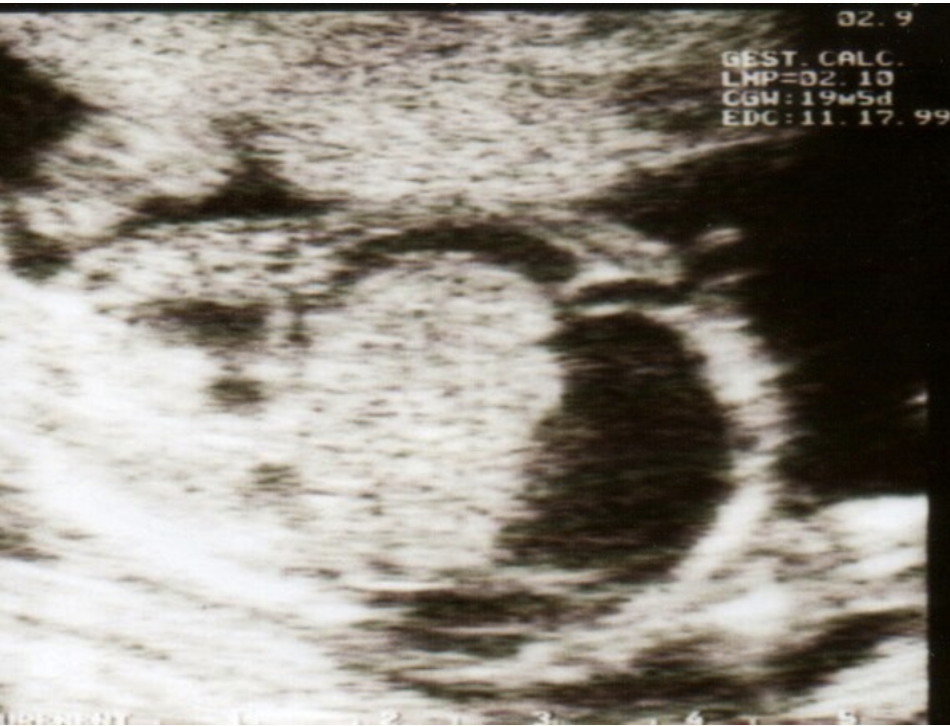

The given USG shows _____ sign and _____ sign in congenital hypertrophic pyloric stenosis